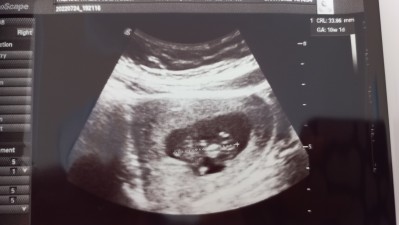

Arkadaşlar ultorosn resminden anlayan var mi ne biçim bakıyor bu doktorlar bıktım adam akıllı doktor bulamamaktan neresi kafa neresi ayak

Yanlış okumadıysam 10w1d yazıyor gebelik yaşi yani bu haftada hiç bir yeri zaten belli olmaz canım topacik bir et parçası henüz anlamamış olman çok normal ")

Renkli ultrason ile baktı o zaman demek ki burada da ölçüm yapmış sadece ve kalp atimina bakmış bir sonra ki kontrolde daha belli olur hale gelir minnos

Kjhhjkl canm bebıs cok kücük:) ultrason cıhaz kalıtelı degılse görüntüde öyle oluyo malesef doktorun cekmesıyle alakalı degıl devlet hastanelerınde klasık ultrasonlar varken ozellerde 3d görüntulerı var daha net daha kaliteli.bebişe gelince başı sag taraf beden solda ayak ve kollar daha yok desek yerı mınnacık cıkıntı 4aya kadr yaklaşık bebek baslsrı bunyelrrıyle aynı buyuklukte oluyo ayaklarıda kısa gelişiyo zamanla netleşecek hayrlı olsun Rabbım sagsaglım kucana almayı nasip etsin

Ortada kalan govdesi. Bacaklarini karnına ,elinin birini de ağzının o tarafa çekmiş

Çok hareketli oluyorlar uygun pozisyonu yakalayıp durdurup foto anca alıyorlar . Ben de ultrasonda çalıştığım için biliyorum. Çok heyecanlı zamanlar oluyor doktorun odasına girince bebeği görmek .siyah beyazların içinde neresi ne diye düşünmek .. siz yargilayanlari bosverin. Sağ salim zamaninda gelir kucağınıza insaaallah